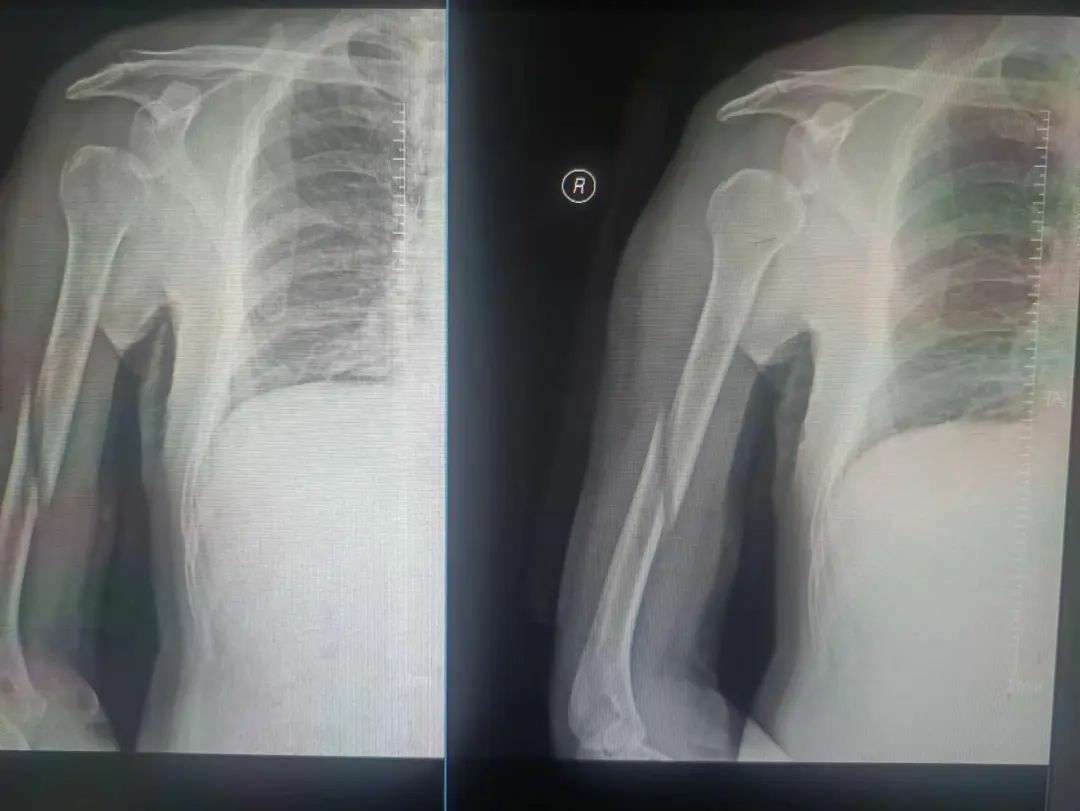

患者为53岁男性,因不慎跌倒,右上臂遭受重创,出现明显的畸形、肿痛以及活动受限。他迅速前往当地医院寻求治疗,经过详细的拍片检查后,被诊断为右肱骨干多段骨折。对此,医师原本建议通过手术治疗来确保患者的康复。然而,该患者由于患有肝硬化,导致凝血功能严重受损,无法接受手术治疗。因此,在伤后四日,患者转至福清市第五医院,希望找到更为合适的保守治疗方案。

第一次拍片

复位后拍片

王征勇接诊后,凭借丰富的临床经验,对患者的病情进行了全面而细致的评估,采用手法复位结合小夹板外固定的方式来进行治疗。随后的影像学检查复查结果显示,患者的骨折对位对线情况良好,但有一处较大的骨片出现了分离移位。王征勇再次进行了审慎的评估,认为当前的对位对线状态是适宜的,可以继续采取保守治疗措施。

伤后43天拍片

伤后43天,患者再次接受拍片复查。这次的结果令人欣喜,骨折块贴合良好,且已有少量骨痂生长。根据这一进展,王征勇指导患者戴着小夹板开始主动进行肩关节功能锻炼。这不仅有助于骨折的愈合,还能加速患者上肢功能的恢复。

2个多月后拍片

在伤后近2个月的随访中,患者再次接受拍片复查。结果显示,骨折对位对线依然良好,且已有大量骨痂生长。这一显著的进步让王征勇决定为患者拆除外固定装置,以便他能更加自如地进行康复锻炼。

6个月后拍片

最终,在伤后近6个月的复诊中,患者恢复良好,已完全恢复正常生活。